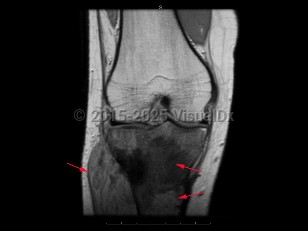

Imaging Studies image of Osteosarcoma - imageId=7912443. Click to open in gallery.  caption: '<span>Coronal T1 MRI sequence  demonstrates an infiltrative mass within the proximal tibial metaphysis  with low T1 signal, periosteal reaction/breakthrough, and an associated  soft tissue mass. These findings are compatible with an osteosarcoma.</span>'

Coronal T1 MRI sequence demonstrates an infiltrative mass within the proximal tibial metaphysis with low T1 signal, periosteal reaction/breakthrough, and an associated soft tissue mass. These findings are compatible with an osteosarcoma.